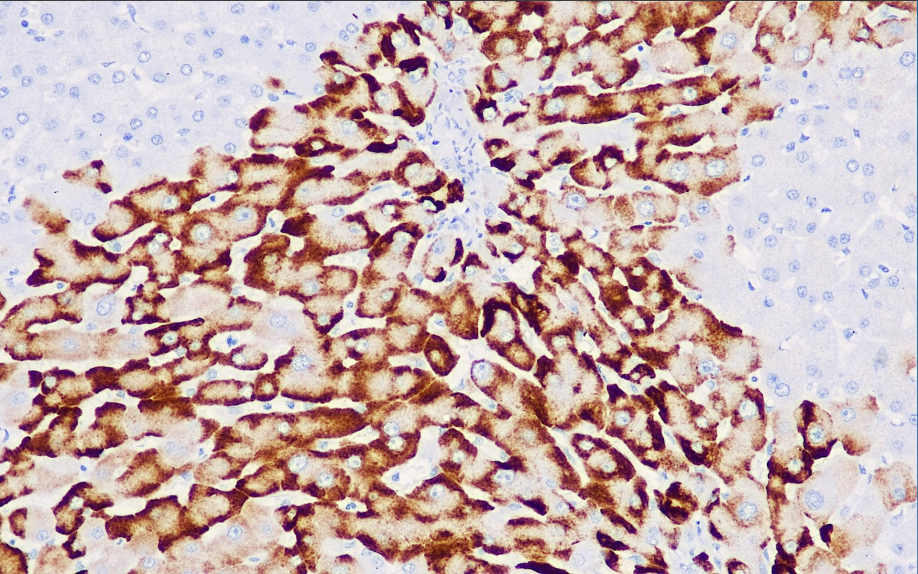

Positive control: HBV-infected liver tissue

This antibody reacts with the ad/ay subtype of hepatitis B virus surface antigen and shows diffuse coloration in the cytoplasm of infected tissues. It is mainly used in liver tissues infected by the hepatitis B virus, and is also used in studies of the correlation between hepatitis B virus infection and cirrhosis and hepatocellular carcinoma.